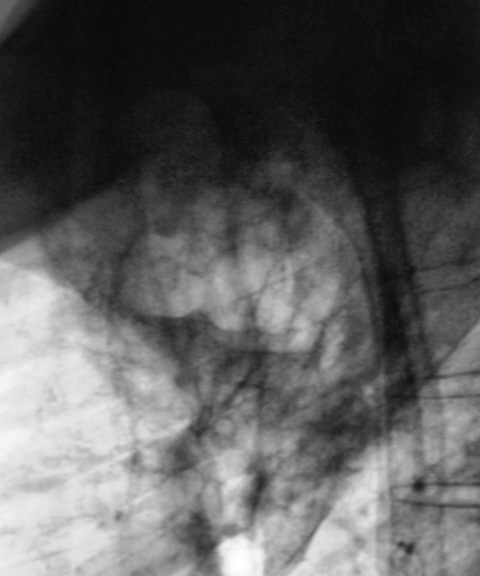

Пациент в 2007, 2008 гг. проходил профилактическую флюорографию - иллюстрации ниже. При прохождении флюорографиив 2009 г. "картинка" резко отличается от предыдущих.

Произвели дообследование пациента согласно стандарту.

По поводу личного мнения - больше склоняюсь, пока, в сторону абсцесса, однако сомнения терзают и весьма.

А разве не похоже на каверну с толстыми стенками?

Очень похоже,но при микроскопии "палки" не выявлены. Фтизиатр занимается пациентом вплотную. Уже рентгенологически обследовано "окружение" пациента, договорились с областной туб. больницей по поводу госпитализации. Но, вот полость какая-то не совсем типичная, хотя локализация и общий вид верхушки прямо указывают на "специфику".

Не должно быть туберкулёзом. Полость большая, а отсевов нет.

Как Вам версия распадающегося рака?